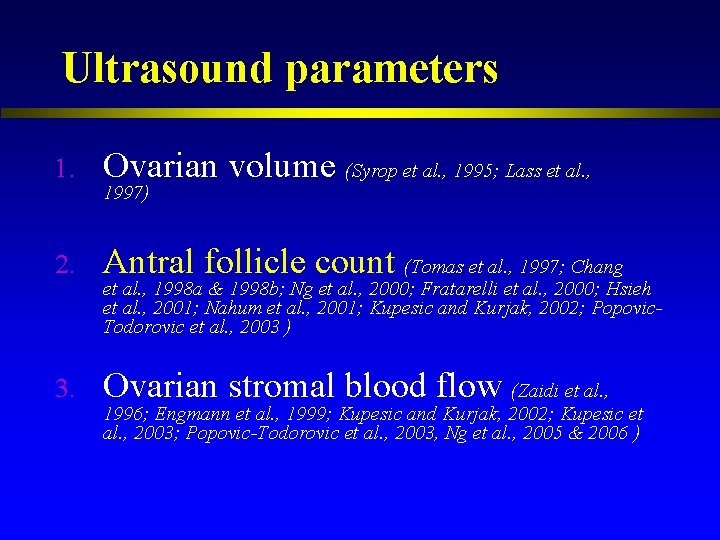

Ultrasound parameters 1. Ovarian volume (Syrop et al. , 1995; Lass et al. , 2. Antral follicle count (Tomas et al. , 1997; Chang 3. Ovarian stromal blood flow (Zaidi et al. , 1997) et al. , 1998 a & 1998 b; Ng et al. , 2000; Fratarelli et al. , 2000; Hsieh et al. , 2001; Nahum et al. , 2001; Kupesic and Kurjak, 2002; Popovic. Todorovic et al. , 2003 ) 1996; Engmann et al. , 1999; Kupesic and Kurjak, 2002; Kupesic et al. , 2003; Popovic-Todorovic et al. , 2003, Ng et al. , 2005 & 2006 )